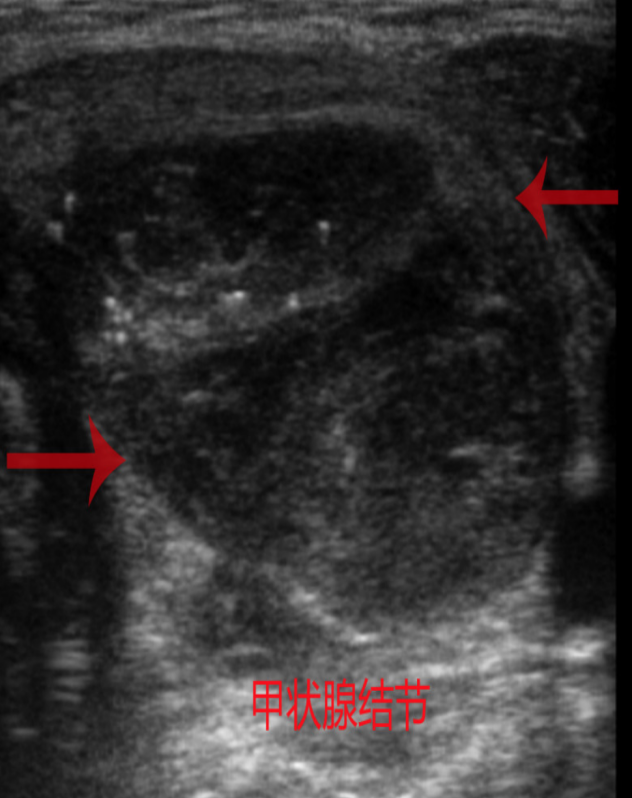

甲状腺结节,顾名思义就是甲状腺里长了小包块。根据包块的影像学特征分为囊性、囊实性和实性结节。根据病理类型分为增生性结节(增生活跃的甲状腺正常组织)、肿瘤性结节(良性或恶性)。